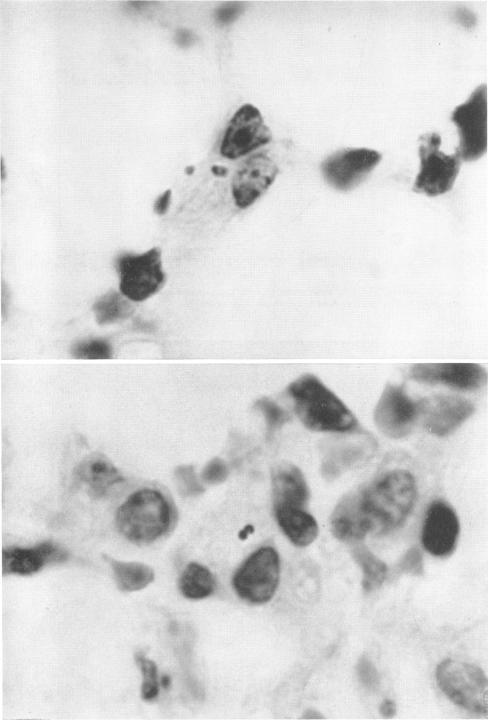

Kass E H, Green G M, Goldstein E

Bacteriol Rev. 1966 Sep;30(3):488-97. doi: 10.1128/br.30.3.488-497.1966.